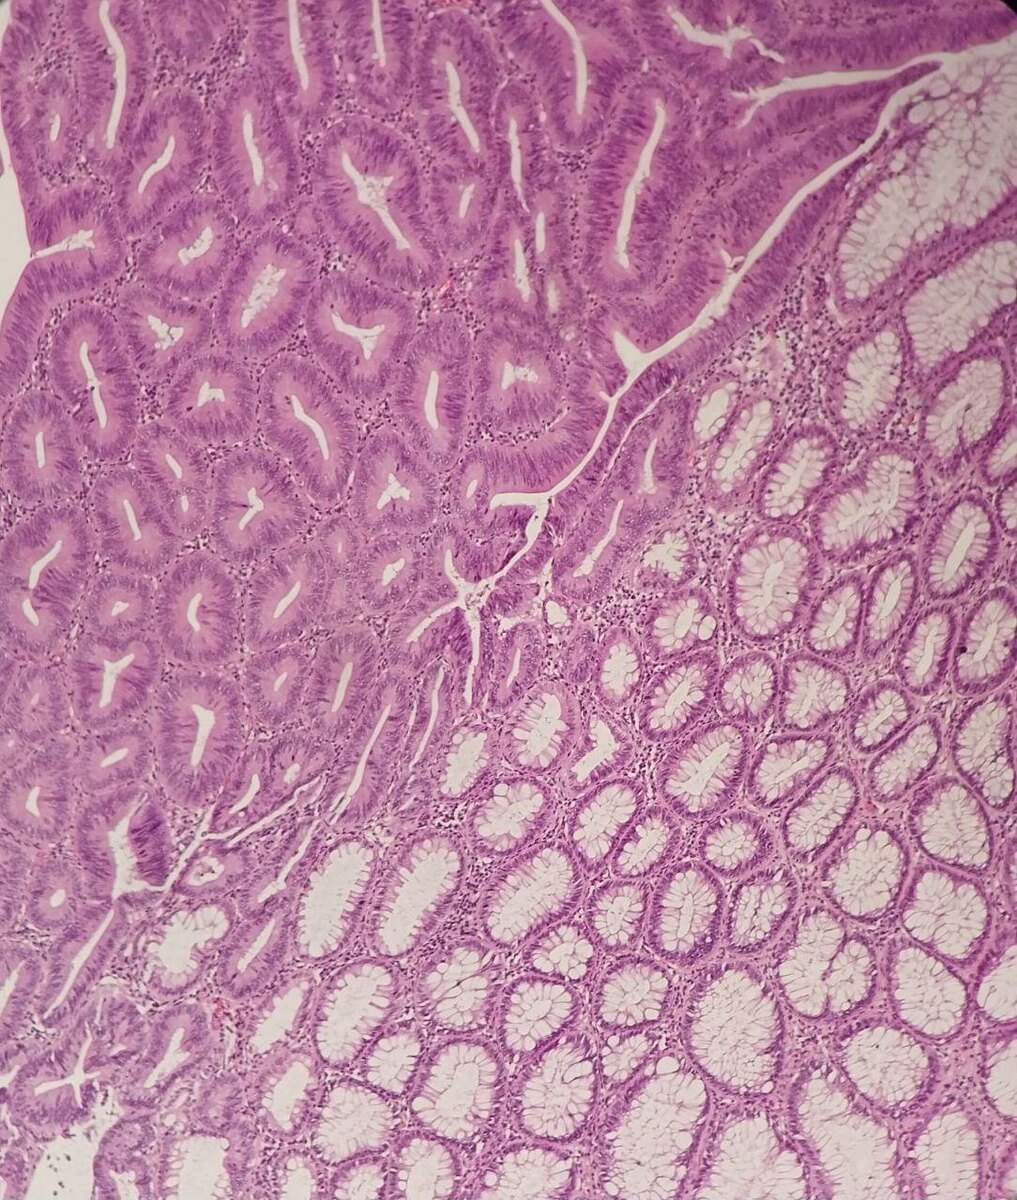

Вот так выглядит момент ДО диагноза.

Коллега, врач-патологоанатом, онкоморфолог,

показала фото из лаборатории.

На снимке — аденома толстой кишки с дисплазией эпителия тяжелой степени.

Проще говоря — клетки уже перестали подчиняться правилам.

Еще чуть-чуть — и начнётся рак.

📊 Так выглядит болезнь, которую можно было остановить, если бы вовремя нашли воспаление, скорректировали питание, проверили микробиом, прошли чекап.